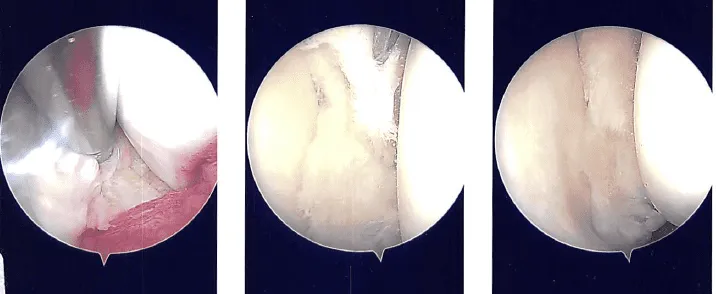

Se creó una incisión lateral para el portal de entrada cerca de la rótula. Se dio el alcance. La rotura del menisco medial fue visible tras el traslado del endoscopio de la articulación patelofemoral al compartimento medial. El compartimento lateral fue examinado con el endoscopio, y se reveló deshilachamiento del menisco lateral y un desgarro en su cuerno anterior.

Durante la meniscectomía medial, la complicada ruptura del cuerno posterior y del cuerpo del menisco medial se eliminó utilizando upbitters y mordedores rectos. Se utilizó Shaver para vaciar el quiste parameniscal y los márgenes de la debrida y el transecto.

Se descubrió que la rodilla estaba intacta cuando se avanzó el endoscopio hacia la región intercondilar. El compartimento lateral recibió la mira. El cuerno anterior del menisco lateral estaba desgarrado y el borde medial del menisco lateral estaba deshilachado. El menisco fue limpiado con una cuchilla.

Había márgenes de equilibrio. Se capturaron y almacenaron las imágenes finales. En los cóndilos femoral medial y lateral no había artritis. Había artritis de grado 1 a grado 2 en la meseta tibial lateral.

El endoscopio se trasladó a la articulación patelofemoral, donde no se detectó artritis ni en la rótula ni en la troclea. Se tomaron y guardaron las fotos finales. La rodilla estaba completamente lavada.